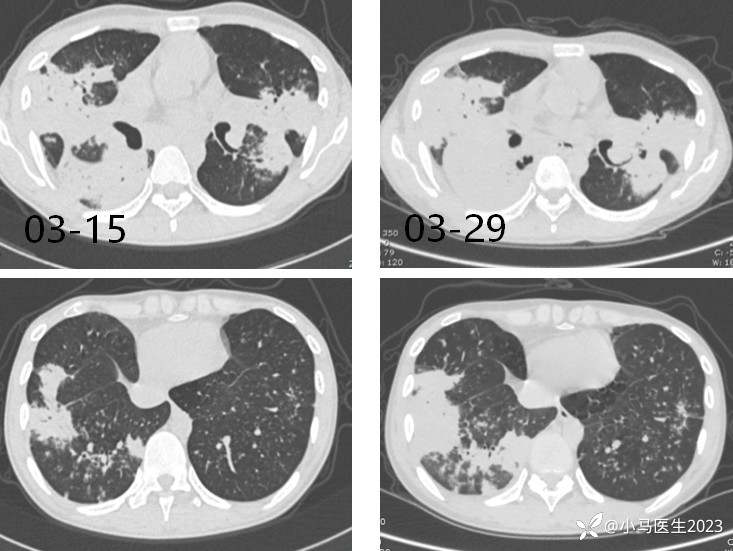

患者要求经验性治疗,予甲泼尼龙40mg qd×7天,03-15复查

胸部CT无明显变化,予口服甲泼尼龙40mg带药出院

第四次入院 03-29

03-29复查胸部CT进展

胸部CT对比

换用两性霉素B脂质体

05-12

05-27

对比